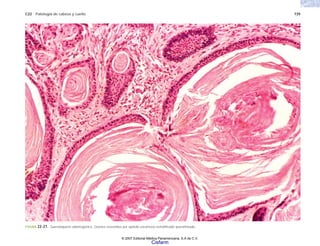

puma en la montaña. El padecimiento era un castigo

divino por la violación de alguna regla, o el resultado